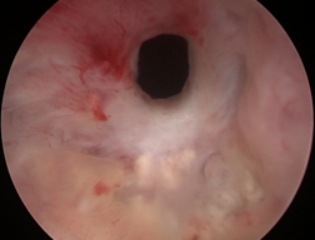

术前针孔样改变